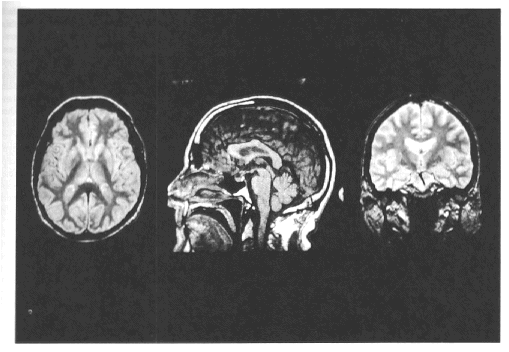

Figure 1.

MRI scans acquired in axial (A), coronal (B) and sagittal (C) planes.  All images were acquired with a field of view of 24 cm, NEX = 1, and 256 x 256 matrix.  Left:  Axial image, 5-mm thick, passing through the lateral ventricles and basal ganglia.  Image was acquired in an oblique plane parallel to the AC-PC line. Image was acquired using a spin-echo sequence, gated to achieve an effective TR of >2400 ms with one excitation for each of 256 phase encodes and TE of 20 ms.  Center:  Mid-sagittal image, 3 mm thick, acquired using a single-echo pulse sequence (TR=600 msec; TE=20 msec), collected without using internal anatomical landmarks. Image highlights the corpus callosum, brain stem and cerebellum.   Right:   Coronal image, 3 mm thick, passing through laeral ventricles and temporal lobes.  Image was acquired in a plane perpendicular to the AC-PC line using a multiecho, flow compensated, cardiac gated pulse sequence (TE=40 msec; effective TR·2800 msec).